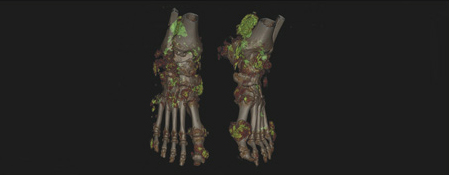

DECT-undersøkelse supplerer ikke-invasive metoder ved å gi farger til materialer med kjemisk forskjellig komposisjon (11). CT-skanneren bruker to forskjellige spenninger, vanligvis 80 kV og 140 kV. Etter bearbeiding av data kan urinsyrekrystaller/tophi skilles fra ben, bløtdelsvev og hydroksyapatitt og visualiseres (fig 1). Denne metoden er relativt ny og fungerer best ved etablert sykdom med en viss mengde avleiring av krystaller.

Metoden er tilgjengelig ved en rekke norske sykehus og kan dermed ha sin plass når diagnosen ikke er sikker eller når man ønsker å evaluere om effektiv behandling har redusert mengden av/størrelsen på tophi.